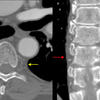

paraspinal interface